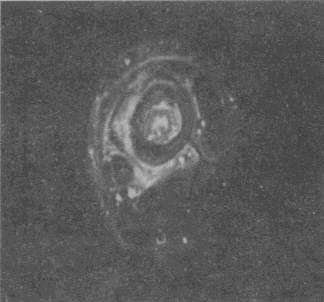

男,33岁,有发热,小腿局部有疼痛,红肿并有压痛,结合图像,最可能的诊断是

男,33岁,有发热,小腿局部有疼痛,红肿并有压痛,结合图像,最可能的诊断是<img border="0" style="width: 324px; height:

[单选题]男,33岁,有发热,小腿局部有疼痛,红肿并有压痛,结合图像,最可能的诊断是A.骨髓炎B.脂肪瘤C.未见异常D.骨髓瘤E.骨化性肌炎

男,33岁,有发热,小腿局部有疼痛,红肿并有压痛,结合图像,最可能的诊断是

[单选题]男,33岁,有发热,小腿局部有疼痛,红肿并有压痛,结合图像,最可能的诊断是A.骨髓炎B.脂肪瘤C.未见异常D.骨髓瘤E.骨化性肌炎

男,33岁,有发热,小腿局部有疼痛,红肿并有压痛,结合图像,最可能的诊断是()

[单选题]男,33岁,有发热,小腿局部有疼痛,红肿并有压痛,结合图像,最可能的诊断是()A . 骨髓炎B . 脂肪瘤C . 未见异常D . 骨髓瘤E . 骨化性肌炎

男,33岁,有发热,小腿局部有疼痛,红肿并有压痛,结合图像,最可能的诊断是()

[单选题]男,33岁,有发热,小腿局部有疼痛,红肿并有压痛,结合图像,最可能的诊断是()A .骨髓炎B .脂肪瘤C .未见异常D .骨髓瘤E .骨化性肌炎